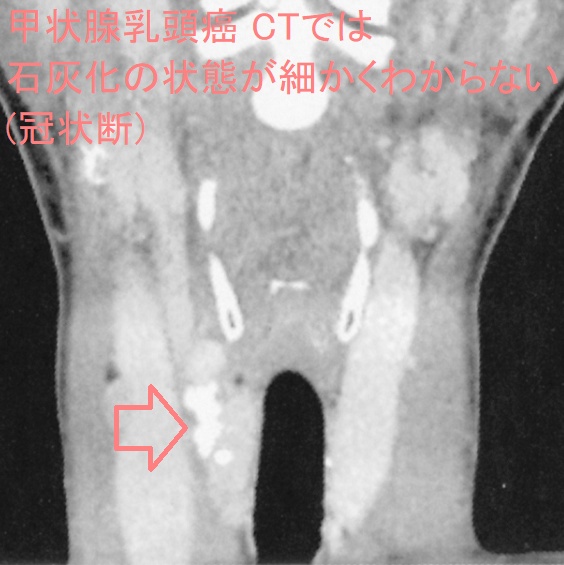

- 精密でも5mm、通常10mmスライスで撮影するため、解像度が悪く、5-10mm以内の病変が写らない確率が高い[甲状腺超音波(エコー)検査は、3mm大(条件次第では2mm大)の甲状腺癌でも見つかります。また、甲状腺乳頭癌において最大の特徴である微細な砂粒状石灰化(psammoma body)は5mm未満のため、CT・MRIでは写りません。]

同時に、CTでは甲状腺癌の微細石灰化(5mm以下)が写らない。さらに、細かい石灰化の状態を評価できない。